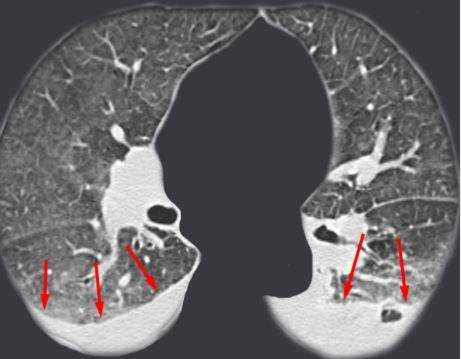

Фото томографии грудной клетки

Расшифровка снимков происходит в тот же день. Полученные изображения анализирует врач-рентгенолог, который и выдает заключение. Определить верный диагноз непросто, ведь среди нескольких десятков оттенков черного, серого и белого необходимо вычленить несоответствующий норме и интерпретировать результат. Представим Вашему вниманию несколько фото томографии грудной клетки:

КТ без контраста у пациента с интерстициальным заболеванием легких в анамнезе и трансплантацией правого легкого показывает суженный участок анастомоза правого бронха (красная стрелка). Собственное левое легкое уменьшено в размерах, с признаками бронхоэктазов, бронхиолоэктазов (черная стрелка). Сужение центрального дыхательного пути на выдохе у трансплантированного легкого (синяя стрелка).

Выпот (красные стрелки) в обеих плевральных полостях.